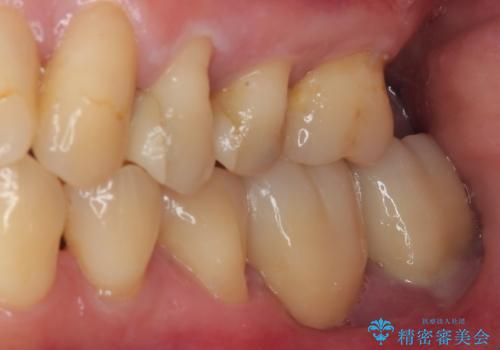

ブリッジから膿が出る 奥歯のインプラント治療

- ブリッジの土台から膿が出るとのことで来院された患者様です。

不均衡で無理な力がかかってしまうブリッジを装着したため、最後臼歯周辺の歯槽骨が溶けている状態でした。

上顎は最後臼歯が欠損しているため、ブリッジの土台は抜歯し、元々の欠損部にインプラントによる補綴治療を行うこととしました。